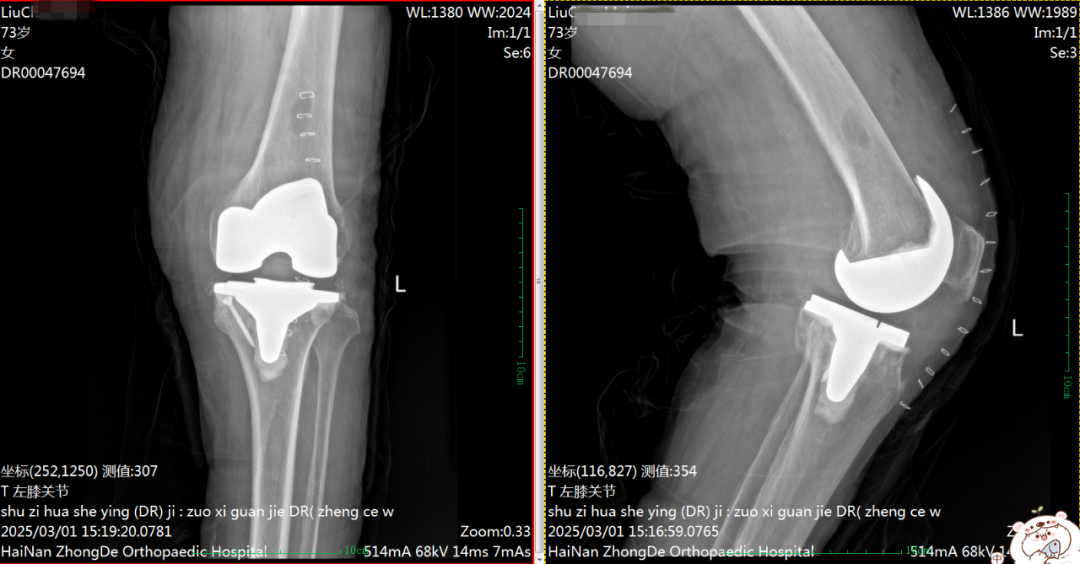

术后DR片

同样,76岁的陈阿公,右膝关节疼痛伴活动受限1年多,辗转多家医院,疼痛症状仍反复出现。听闻付昆教授是这方面的专家,遂慕名而来。鉴于患者身体状况和膝关节病情程度,付昆教授团队为期实施了“右侧全膝关节置换术”,术后恢复良好!